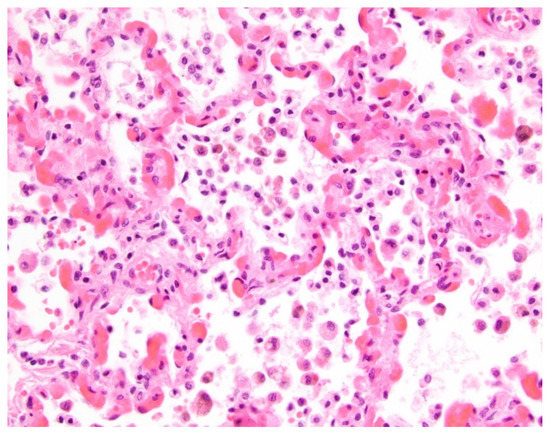

- Pogoriler, J.E.; Kulik, T.J.; Casey, A.M.; Baird, C.W.; Mullen, M.P.; Jenkins, K.J.; Vargas, S.O. Lung pathology in pediatric pulmonary vein stenosis. Pediatr. Dev. Pathol. 2016, 30, 219–229. [Google Scholar] [CrossRef]

- Callahan, R.; Gauthier, Z.; Toba, S.; Sanders, S.P.; Porras, D.; Vargas, S.O. Correlation of intravascular ultrasound with histology in pediatric pulmonary vein stenosis. Children 2021, 8, 193. [Google Scholar] [CrossRef] [PubMed]